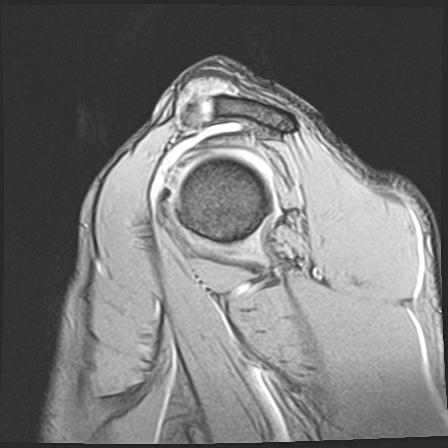

60058 3/9 11/4 右肩 2R+MRI 73歳男性 肩腱板損傷